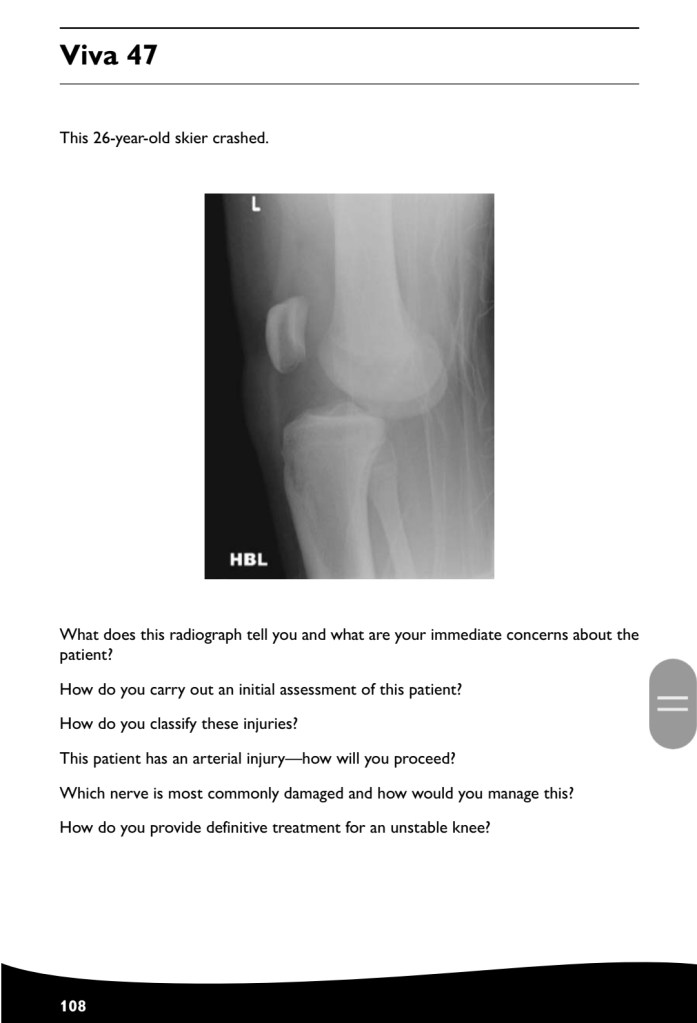

Revision how to answer your case